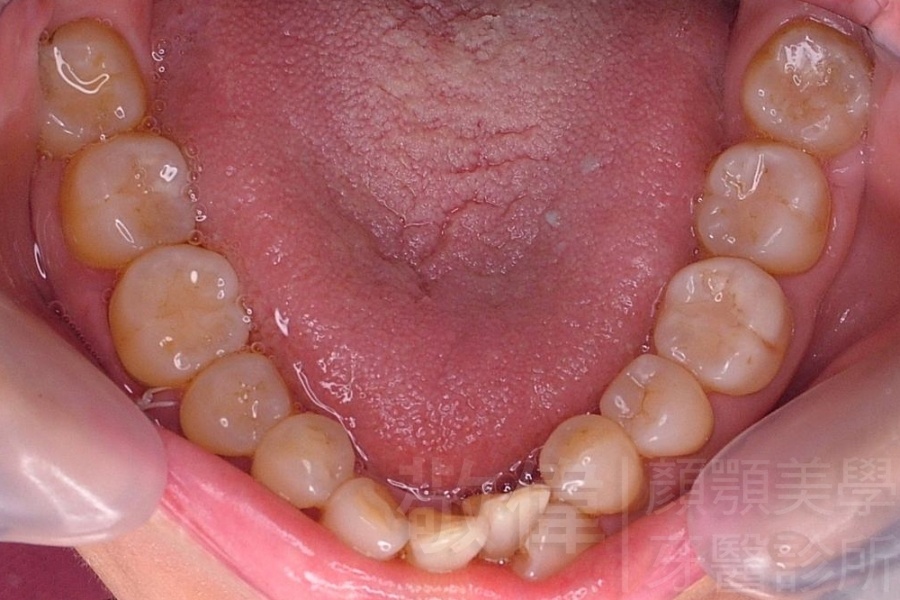

齒顏矯正/上顎暴牙且牙齒極度混亂

矯正前-右   矯正前-正   矯正前-左

矯正後-右   矯正後-正   矯正後-左

矯正前-上   矯正前-下

矯正後-上   矯正後-下

<個案說明>

上顎暴牙且牙齒極度混亂,經由矯正之後,臉型大幅度改善,牙齒的排列更加的整齊健康。相較於之前眼神充滿精神,自信心展現無遺。